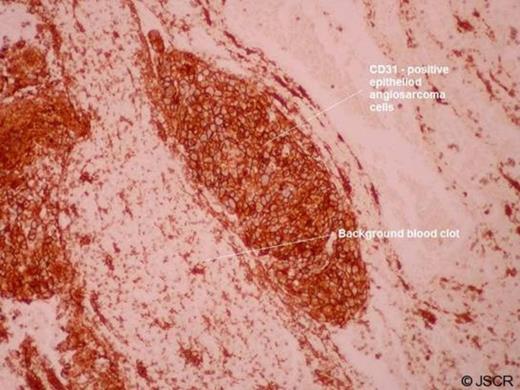

Histology from the incision biopsy revealed a diagnosis of epithelioid angiosarcoma (Figure 2) which is known to be associated with the development of vascular lakes.

(CD31 immunohistochemistry: Immunoperoxidase, original magnification x100)

Histologically these tumours consist of solid and infiltrative sheets of epithelioid cells characterised by large, oval to round cells with abundant eosinophilic cytoplasm, vesicular nucleus and eosinophilic nucleolus.(3)

In most cases there are vascular channels or cystically dilated spaces. Vascular lakes are therefore a common finding associated with these types of sarcoma. A distinctive “starry-sky” histological pattern has also been reported in epithelioid angiosarcomas. Immunohistochemically the neoplastic cells show positivity for endothelial cell markers such as CD31, CD34, factor VIII-related antigen, and vimentin.(4-5)